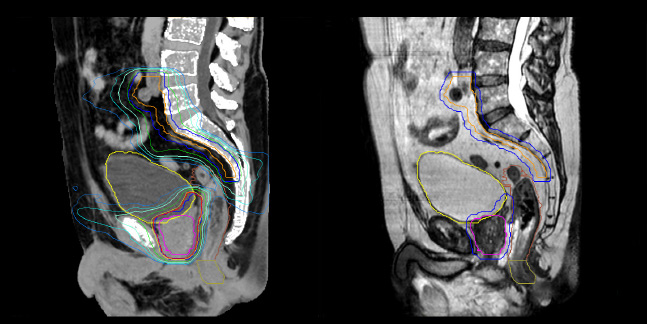

MRCAT Pelvis is flexible, yet robust

Dr. Champion appreciates that MRCAT Pelvis also enables rectal cancer simulation in the prone position, allowing the digestive anatomy to be moved away from the treatment volume by projecting them forward.

“The irradiation volumes for a rectal cancer are essentially posterior and lateral, so good sparing of the digestive structures improves tolerance of the treatment,” he says. “Prone positioning can also be applied to anal cancer simulation. This position enables the gluteal muscles to be moved apart, which significantly reduces the toxicity associated with radiation concentrating in the folds.”

MRCAT Pelvis also allows an up to 36-centimeter FOV in the feet-head direction, permitting creation of treatment plans covering extended pelvic targets.

“The large field-of-view is definitely useful and a must-have functionality,” Dr. Champion observes. “For several patients, we have treated the lymph nodes where the radiation fields are longer than 30 centimeters. In our practice, contouring of the pelvic lymph node areas is indicated in prostate cancers of intermediate or high risk. Rectal and anal canal cancer are also irradiated in the lymph node drainage areas. The cranial limit of this elective lymph node irradiation extends up to the aortic bifurcation, which often corresponds to the L4-L5 vertebral disc.”